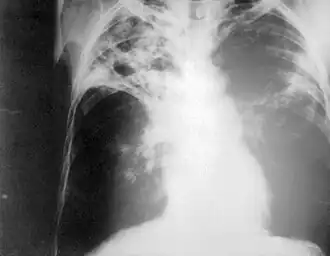

Chest radiography showing advanced bilateral pulmonary tuberculosis. Source: CDC | |

Chest photofluorography, or abreugraphy (better known as mass miniature radiography in the UK and miniature chest radiograph in the US), is a photofluorography technique for mass screening for tuberculosis using a miniature (50 to 100 mm) photograph of the screen of an X-ray fluoroscopy of the thorax, first developed in 1936.